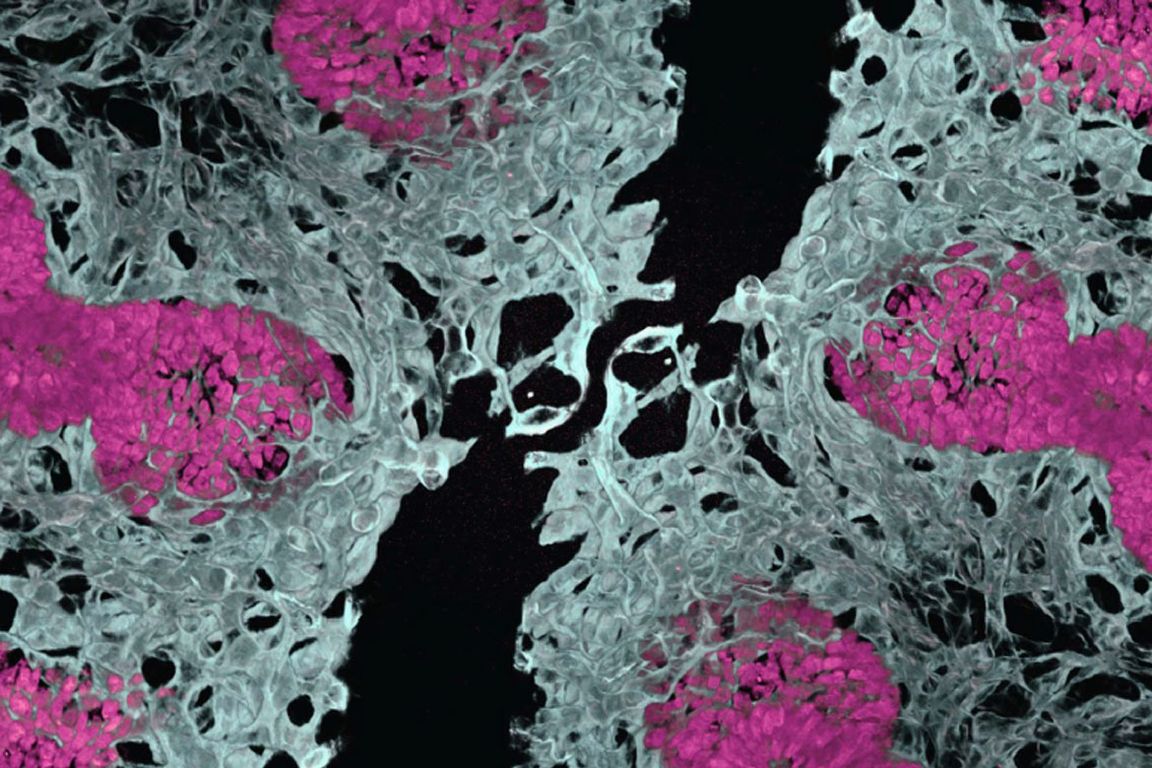

To solve this problem, the team initially tried the conventional assembly approach of growing organ components separately, using fluorescent markers to track different cell types, then combining them at a later stage. Red cells were supposed to become blood vessels, while green cells were meant to become lung tissue.

"We expected red-colored vascular networks and green-colored epithelium," explained Gu, who's also an associate professor of anesthesiology and perioperative medicine at UCLA. "But we actually found red-colored vascular networks and red-colored epithelium, meaning both cell types were surprisingly developing at the same time from the same starting material.”

By allowing lung tissue and blood vessels to grow together from the beginning, the resulting mini-organs demonstrated greater cell type diversity, better three-dimensional structure, improved cell survival and more mature development compared to previous lab-grown organ models.